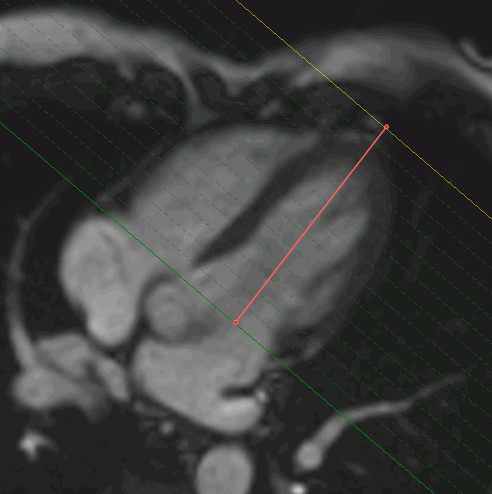

To evaluate the left ventricle extension, you need the SAX and the LAX merged series to be loaded to the Cardiac analysis tab (see Section 8.1.1).

In the window with the SAX merged series, choose the slice for the upper plane of the mitral valve and mark a point in the center of the mitral valve.

Go to the slice corresponding to the left ventricular apex and mark a point in the center of the apex.

When you mouse over a point in the window with the SAX merged series, you see a pop-up tip with the type of the point, Mitral or Apex.

In the window with the LAX merged series, the left ventricle extension is marked with a line (Fig. 8.5).

In multiphase series, the left ventricle extension may be determined for each phase.